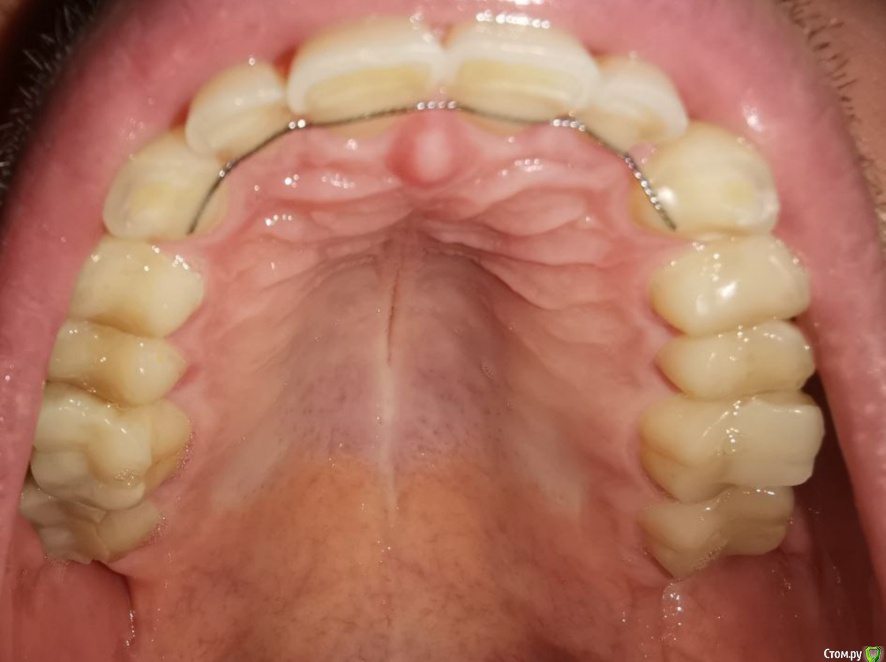

Мне 30 лет, лет 5 назад стоматолог-терапевт заметил излишнюю стираемость, была долгая эпопея с ортодонтическим лечением и вот наконец в прошлом месяце сняли брекеты и теперь настало время ортопедического.

Врач, который работает в паре с ортодонтом настаивает на полном протезировании (спереди виниры emax, сзади накладки так же из керамики). Со слов врача после диагностики сустава стало понятно, что чем выше поднимем прикус тем лучше, так должен уйти бруксизм, который сейчас присутствует.

Альтернативное мнение, которые я получил, что можно сделать накладки только на 5/6/7 со всех сторон, восстановить клыки композитом для "клыкового ведения" и пока все - полное протезирование всегда успеется. Может быть немного пожертвовав высотой прикуса.

п.с. На некоторых зубых есть временные накладки, которые делали на время отродонтического лечения.